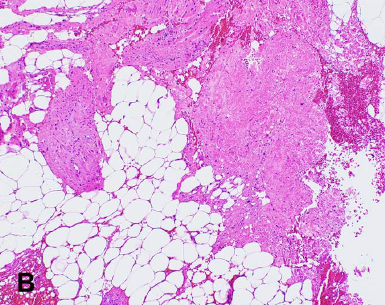

🧬✨ POLE-mutated endometrial cancer → ultramutated biology & excellent survival 🌟